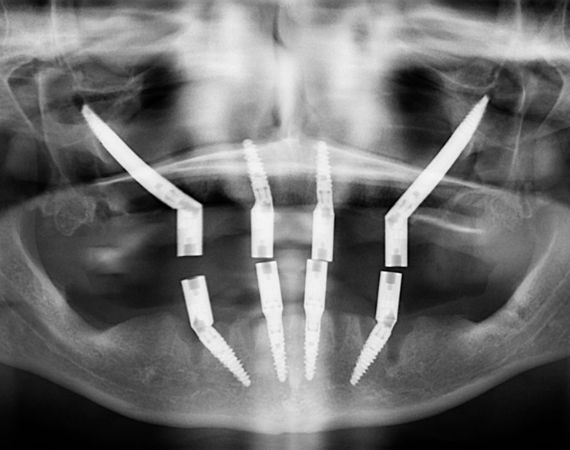

A diferencia de los implantes convencionales, que se colocan directamente en el maxilar, los implantes zigomáticos se insertan mediante una intervención quirúrgica que atraviesa o bordea el seno maxilar para alcanzar el hueso cigomático. La colocación requiere un estudio previo con imágenes 3D (como una tomografía CBCT) para planificar con precisión la longitud, la dirección y la posición de los implantes.